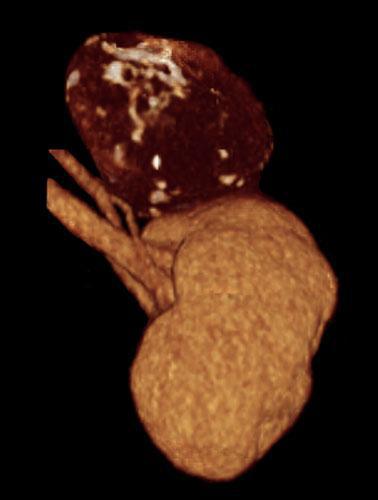

Quiste renal multitabicado e hipernefroma